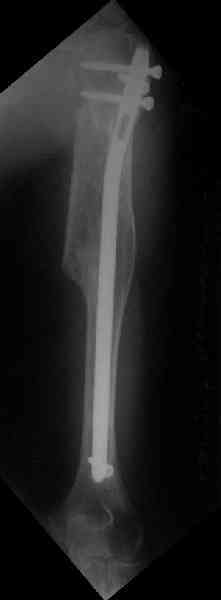

Здесь нет необходимости в серкляже. Вмешиваться на промежуточных отломках приходится, если есть угроза перфорации кожи, или промежуточный отломок попал в фасцию, как пуговица в петлю. В приложении сегментарный оскольчатый перелом плеча в проксимальном отделе, фиксированный больщеберцовым стержнем. Как видите, обошлось без серкляжа. Функция полная.